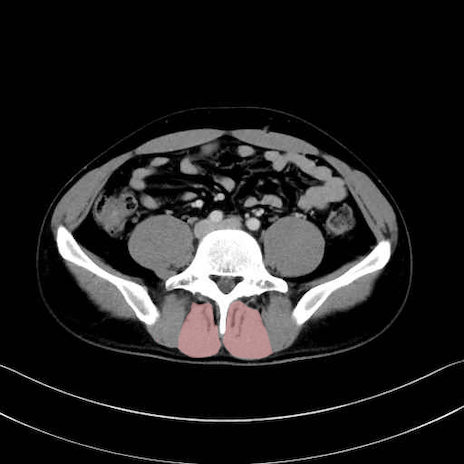

肛門挙筋 (Levator ani)